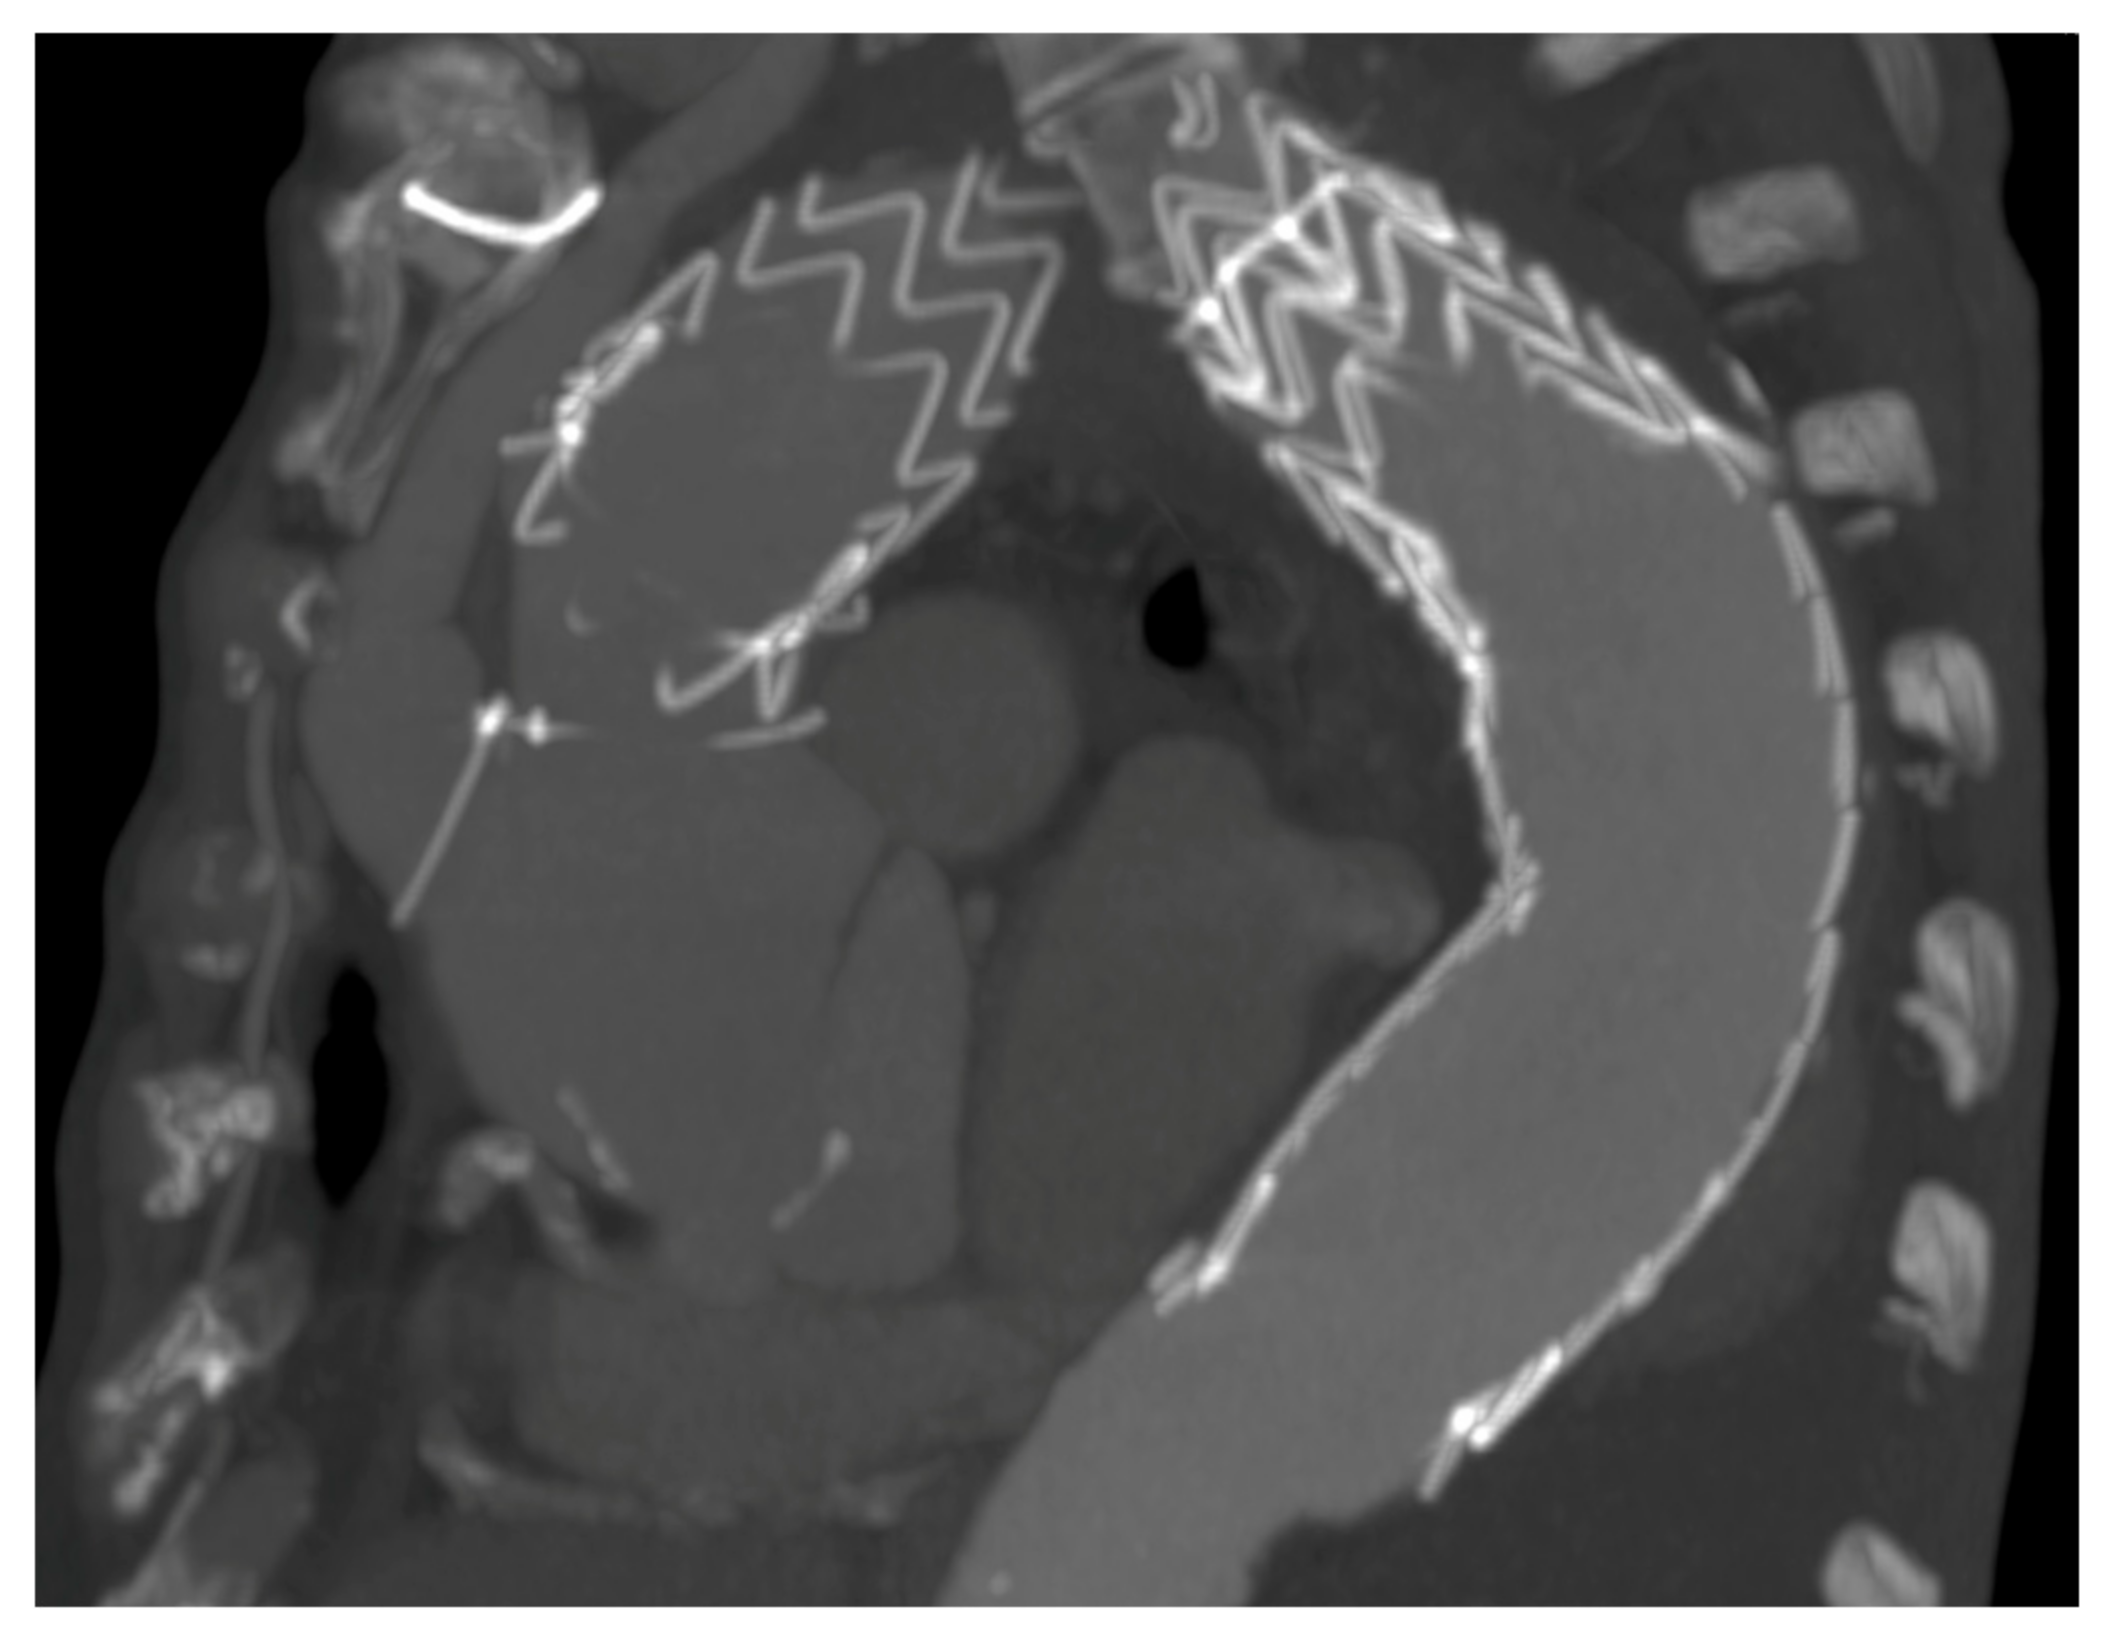

The gold standard of therapy for patients with extensive aorta arch pathology is still nowadays, surgical [9]. Arch repair was first reported by De Bakey and colleagues [10] in the 1950s, but it was in the 1970s, with the introduction of deep hypothermic circulatory arrest, that acceptable rates of neurological complications and mortality were achieved [11]. A milestone in this context was set by Borst and colleagues in 1983 [12] with the first elephant trunk procedure. The development of selective cerebral perfusion strategies [13], the moderate hypothermic circulatory arrest approach [14], the increasing attention to intraoperative monitoring (transesophageal echocardiography, double invasive arterial, near-infrared spectroscopy-based regional oxygenation, multisite temperature, coagulation and spinal cord perfusion pressure monitoring) [15] and the advent of the frozen elephant trunk technique (conceived by Kato in 1994, introduced in Europe in 2001 and widespread in 2005 with the development of the first commercially available hybrid prosthesis) [16,17,18,19] have led to further improvement in outcomes [20]. Despite all these steps forward, surgery is still related to significant morbidity and mortality rates [21] and not all patients are fit enough to undergo frozen elephant trunk surgery. For this reason, in 1991, Volodos and colleagues performed a hybrid aortic arch repair [22] with the purpose of extending the possibility of treatment to those patients with poor physiological reserve due to comorbidities, taking advantage of both open and endovascular procedures. The core principle behind this treatment relies on endovascular exclusion of the pathology following the creation of an adequate proximal landing zone of at least 25 mm on the inner curve by means of supra-aortic transposition (debranching) of (1) (left subclavian artery), (2) (and left common carotid artery also) or (3) (and innominate artery also) arch vessels [15] to allow stent graft deployment in an increasingly proximal position. Debranching options are multiple and can be performed by means of anatomical or extra-anatomical revascularization, with extra- or intra-thoracic approaches [15] according to the Ishimaru aortic arch zone involved [23]. The main potential advantage of this strategy is the avoidance of aortic cross-clamping, hypothermic cardiac arrest and cardiopulmonary bypass. Different types of debranching procedures have been proposed for zone 0 [24]. Type I allow the avoidance of cardiopulmonary bypass but it is not always feasible, as the aortic side-clamping risks aortic rupture or dissection and future ascending aorta dilation could lead to proximal sealing loss. To avoid the latter, it has been proposed to wrap the proximal landing zone with a Dacron graft [5,6]. Alternatively, it is possible to perform a type II debranching. This approach is mandatory in case of ascending aorta dilation (>37 mm). It needs the institution of cardiopulmonary bypass and aortic cross clamping but it can be conducted in mild hypothermia. Patients presenting with distal aortic arch pathology (zone 1 and 2 proximal neck) are usually considered for an endovascular approach with prior left subclavian artery and/or left carotid artery revascularization by means of extrathoracic bypass. The main problem related to the hybrid approach has been the risk of retrograde dissection (Figure 5) and type Ia endoleak. We have not experienced, in our population, acute retrograde dissection, but in one case a chronic dissection of the sinotubular junction was detected at CT scan follow-up. Proximal endoleak was related, mainly, to the stiffness of the first- and second-generation thoracic stent graft that did not allow to conform itself to the anatomy of the aortic arch, particularly in highly angulated (“gothic”) aortic arches with high stress on the aortic convexity and lack of apposition on the inner curvature resulting in a bird-beak configuration.

Figure 5.

Example of retrograde dissection in a type I debranching.